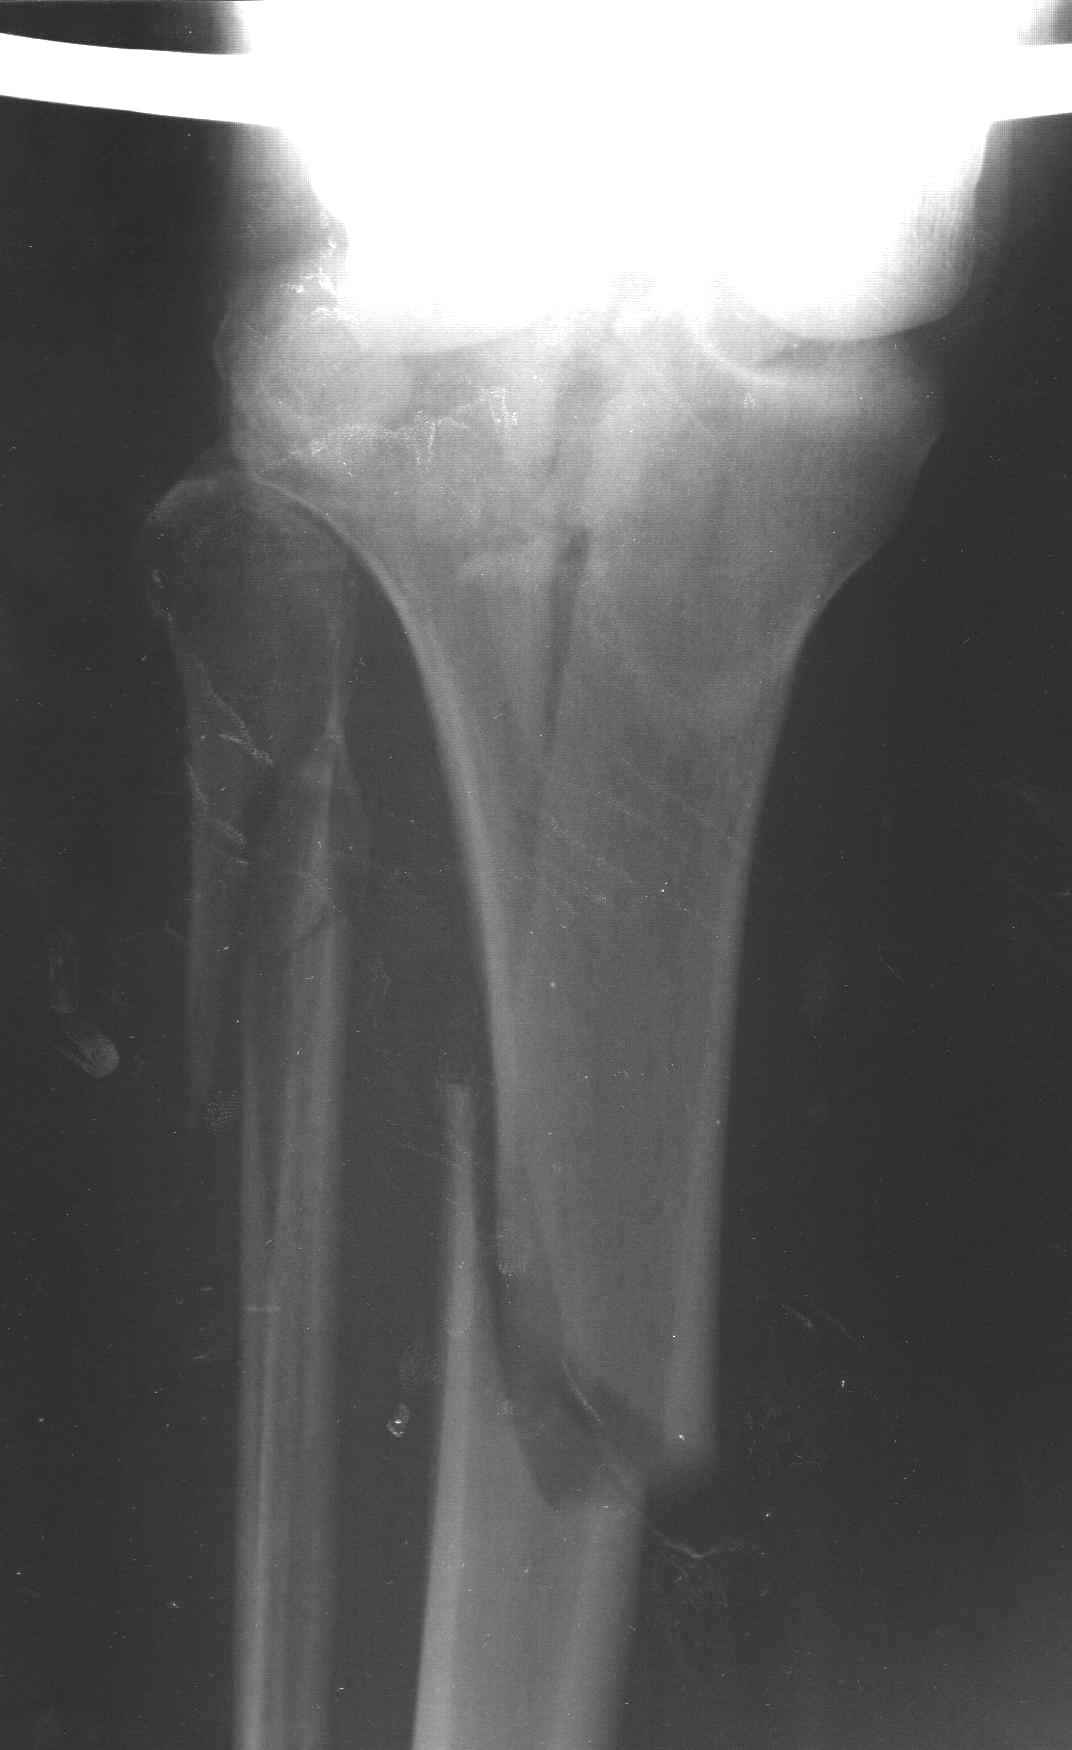

Re: перелом мыщелка и диафиза большеберцовой кости - тактика?

Пациенту сделали КТ - ухитрились сделать на шине Белера (не давал положить прямую ногу) - срезали передний отдел. Планируется на пятницу (24.12) на операцию - синтез длинной мыщелковой LCP-пластиной Synthes :). Отек ближе к слову умеренный (окружность голени +4 см по сравнению со здоровой). КТ и снимок на вытяжении прилагаются.